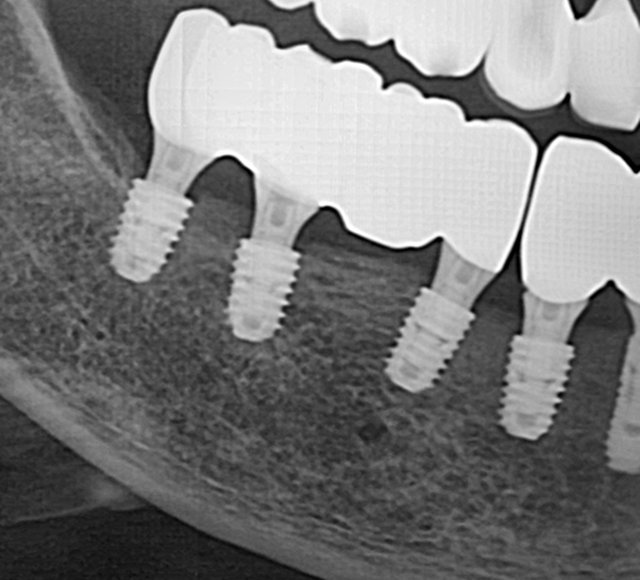

전악 케이스

- 상·하악 전체 보철 설계를 통해 정확한 교합(물림) 회복

- 심미·발음·저작 기능을 종합 고려한 자연스러운 전악 임플란트